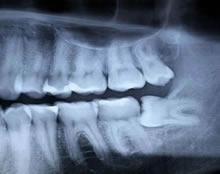

The dentist will be able to assess whether there is sufficient room for the teeth to come through by taking an x- ray which will show the position of the root. Once the x-rays have been taken, the dentist will be able to tell how easy or difficult it will be to remove the tooth. The dentist will then determine whether the tooth should be taken out at the Dental Practice or by a Specialist Oral Surgeon.